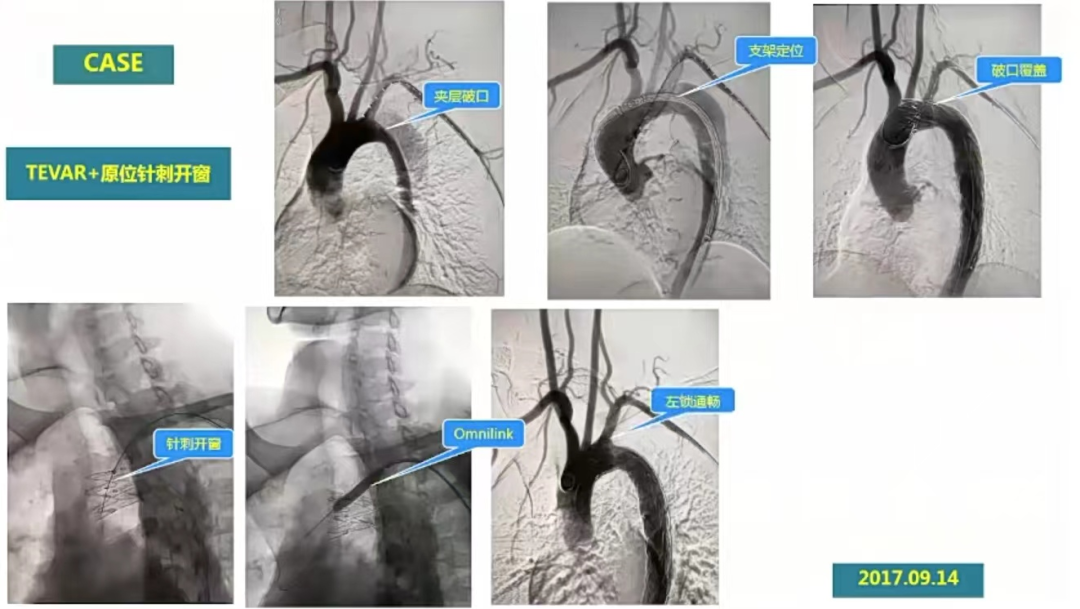

冯骏教授重点从实际病例出发,介绍了球扩支架应用的不同场景。场景一:两例胸主动脉加夹层累计左锁骨下动脉病例,预行TEVAR+原位针刺开窗手术,术中左锁骨下动脉置入一款Omnilink支架,术后造影,显影效果佳,术后3个月、6个月、18个月复查CTA,支架形态、位置良好,血流充盈良好。